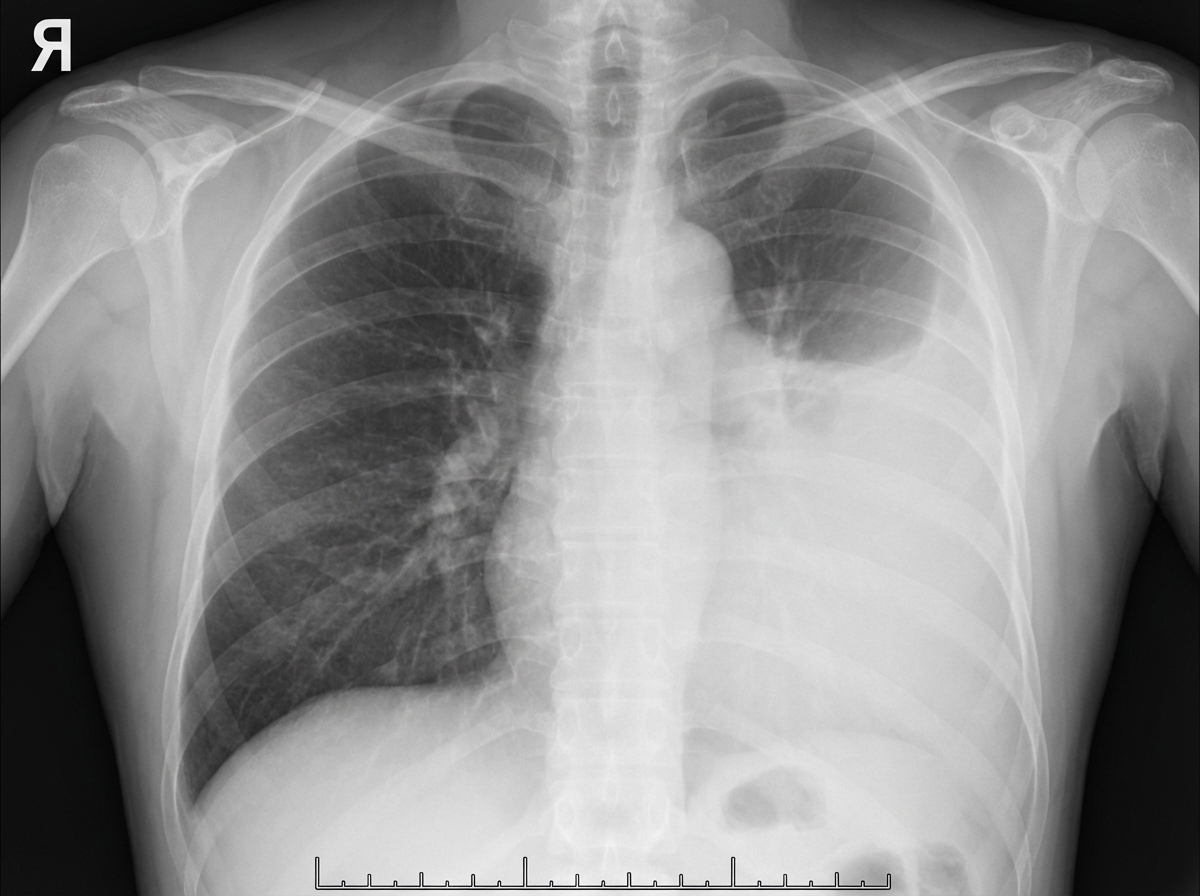

A 45-year-old man in respiratory distress presents to the emergency department. He sustained a stab to his left chest and was escorted to the nearest hospital. The patient appears pale and has moderate difficulty with breathing. His O2 saturation is 94%. The left lung is dull to percussion. CXRs are ordered and confirm the likely diagnosis. His blood pressure is 95/57 mm Hg, the respirations are 22/min, the pulse is 87/min, and the temperature is 36.7°C (98.0°F). His chest X-ray is shown. Which of the following is the next best step in management for this patient?